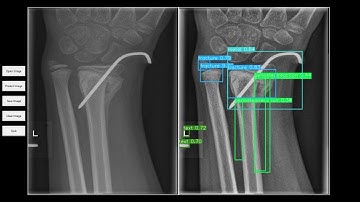

Computer Aided Facial Bone Fracture Diagnosis CA FBFD System Based on Object Detection Model